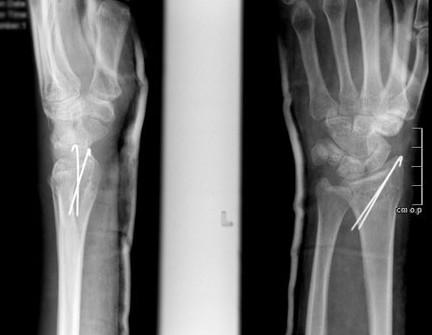

Фиксация спицами или винтами

При небольшом смещении отломков лучевая кость фиксируется при помощи спиц или винтов через маленькие проколы кожи. Согласно стандартному протоколу, гипсовая повязка накладывается на 2 недели, после чего пациент начинает rehabilitate his hand. Спустя 6 недель спицы удаляются.

В некоторых случаях возможно использование саморассасывающихся имплантатов (винтов, спиц), которые не требуют хирургического удаления.